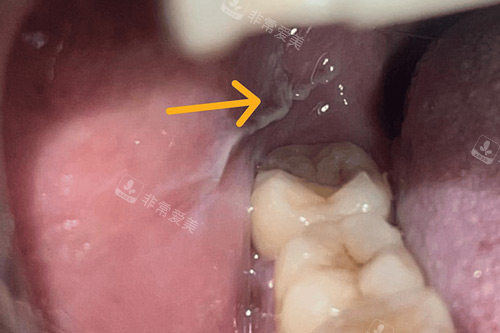

牙齿根管治疗过程图